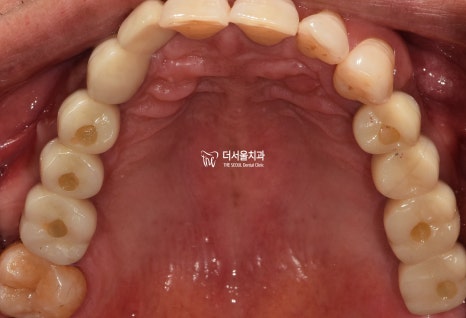

바로 사진부터 보여드리겠습니다.

평소에 구강 관리를 하지 않아서

치태와 치석이 잔–뜩 쌓여 있었고

잇몸이 새빨갛게 부었으며

앞니/어금니 할 것 없이 흔들림을 보였습니다.

아래 사진을 보면

1. 잇몸치료로

치석과 치태를 말끔히 제거했으며

2. 픽스쳐 식립으로

어금니의 기능을 회복시킬 수 있었습니다.